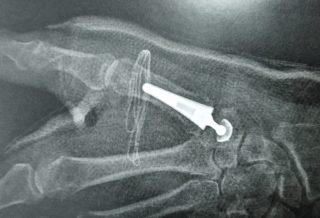

L’arthrose du pouce touche chaque année de plus en plus de femmes et d’hommes. Plus actifs dans leurs vies quotidiennes, cette arthrose devient aujourd’hui très invalidante pour les patients. ...